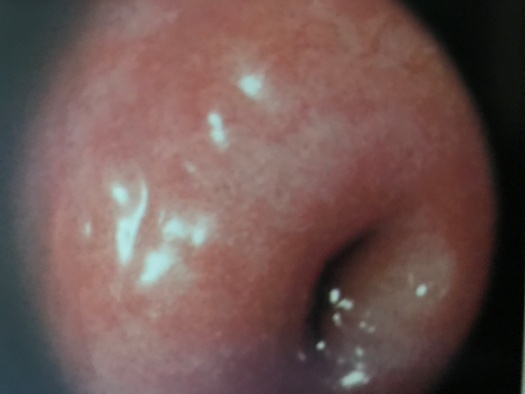

正常宫颈

宫颈表面的细胞在胚胎发育期大致分为两种,以宫颈外口为界,宫颈管内为柱状上皮细胞,宫颈管以外为鳞状上皮细胞。青春期后,在雌激素的作用下,柱状上皮细胞增生,向外爬行,暴露于宫颈管以外,这便是“柱状上皮异位”。由于柱状细胞下方具有丰富的血管网,致使宫颈呈现红色,又由于柱状上皮细胞相互融合,呈绒毛状或颗粒状突起,看起来红红的,糙糙的,貌似“糜烂”。绝经后,雌激素水平低落或缺乏,柱状上皮细胞回缩至宫颈管内,这一现象便不复存在。也不是所有的人,在所有的时期都会出现这种现象,主要取决于宫颈柱状上皮细胞对雌激素的反应性。一言以概之,“宫颈糜烂”是“柱状上皮异位”的表现,是正常生理现象,不是病!更与宫颈癌扯不上边。